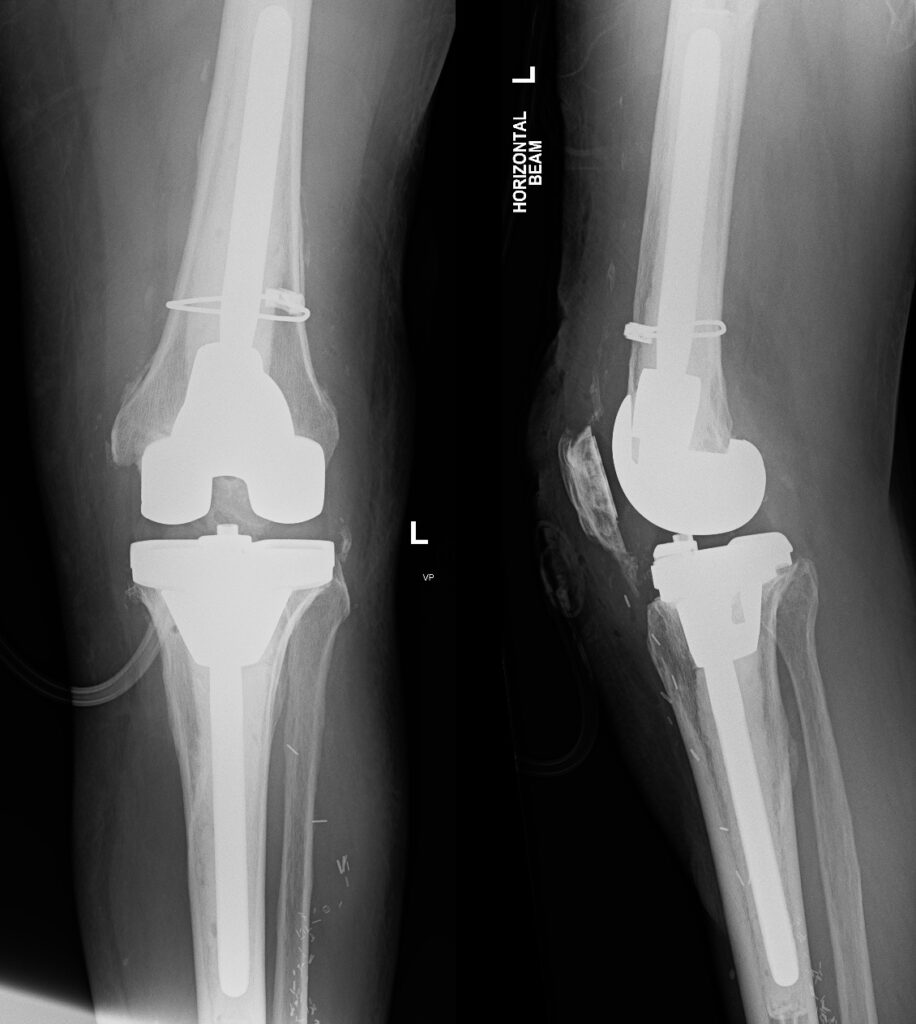

Example of Revision Total Knee Replacement

Xray Revision TKR

A front on view and side on view of a revision total knee replacement